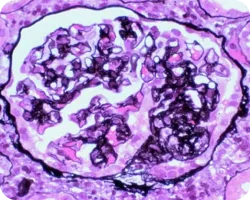

Сегментарный гломерулосклероз (более четырех мезангиальных клеток):

Image

Сегментарный гломерулосклероз

Признаки гипертрофии подоцитов или склероз с локализацией на канальцевом полюсе, являющиеся одной из причин сегментарного гломерулосклероза, связаны с более выраженной протеинурией и более быстрым снижением функции почек. Вместе с тем у пациентов, имеющих описанные признаки, иммуносупрессивная терапия связана с лучшей почечной выживаемостью22.